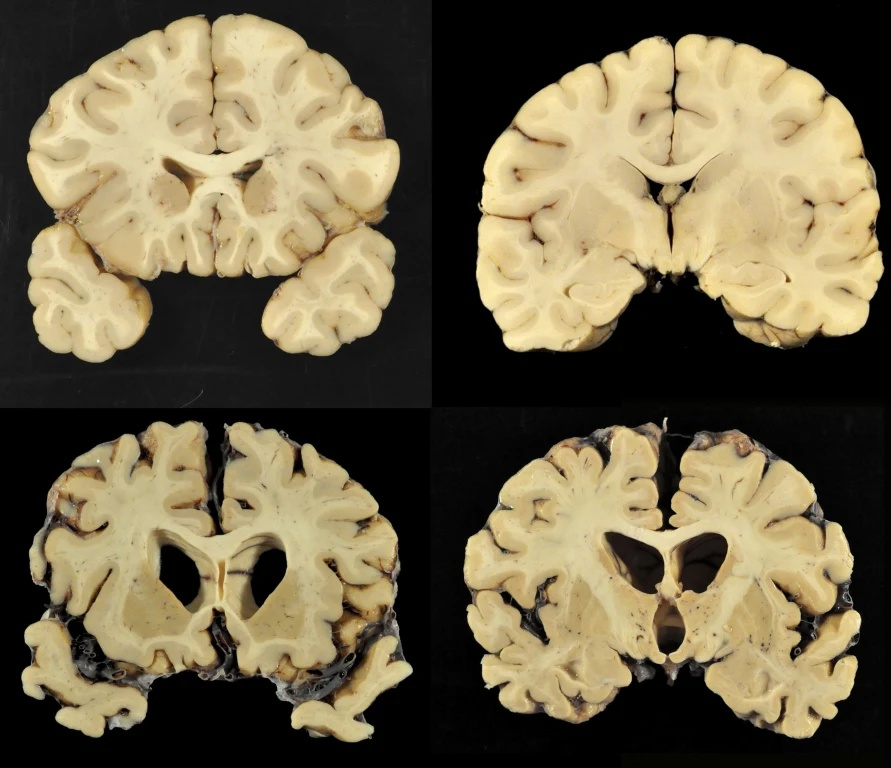

Действительно, как показало вскрытие, Крис Бенуа долгое время страдал из-за множества нелеченых сотрясений головного мозга. Эксперт, проводивший исследование, отмечал тот факт, что мозг Бенуа был так сильно повреждён, что напоминал мозг 85-летнего больного болезнью Альцгеймера, а ещё одно сотрясение мозга могло привести к тяжёлой деменции и вытекающим из этого серьёзным поведенческим проблемам. Всё это говорит о том, что спортсмен страдал от ХТЭ. Но неужели раньше об этом заболевании никто не слышал?

И даже несмотря на то, что медицина шагнула далеко вперёд с момента первого описания болезни, до сих пор точный диагноз ХТЭ можно поставить только на столе у судмедэксперта, а лучшей профилактикой является прекращение употребления гормональных препаратов, снижение количества контактов головы и пола/кулаков/ног/коленей/локтей/стульев и т.д. до минимума и терапия, схожая с той, что назначают людям, страдающим Альцгеймером. Как Вы понимаете, для многих профессиональных спортсменов это означает окончание их карьеры, а потому многие просто скрывают первые признаки ХТЭ до последнего. Далее опишу парочку самых любопытных случаев из современной истории.